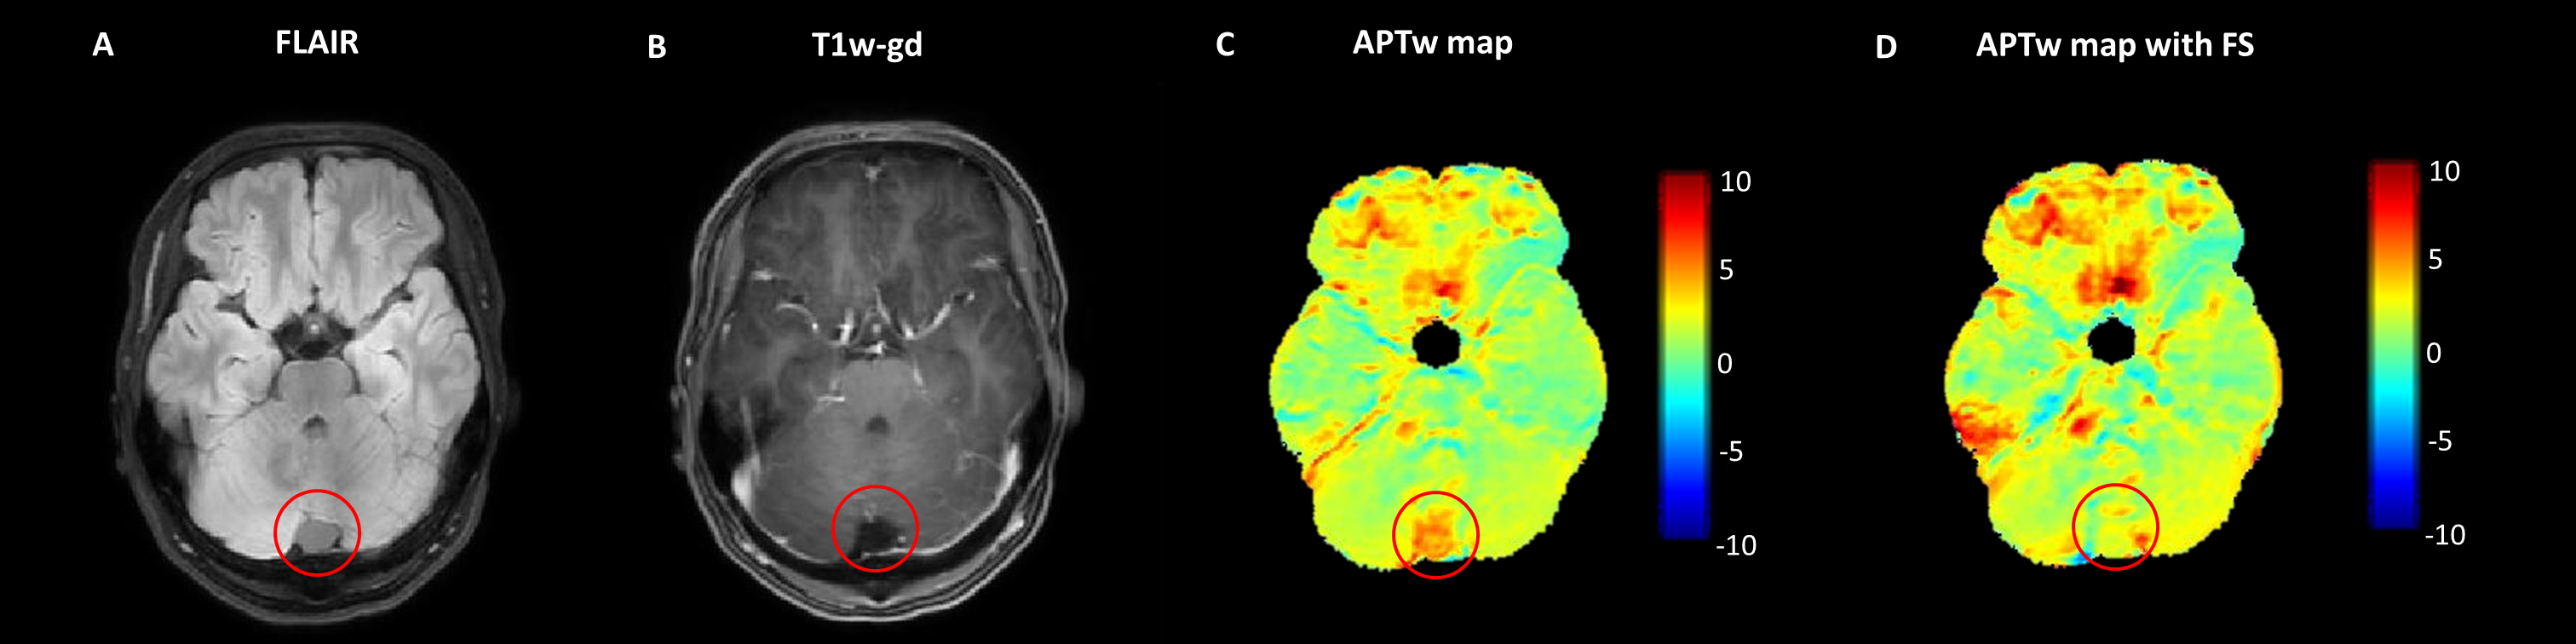

Z-spectra were normalized with respect to the frequency offset at -1560 ppm (S0). B0-correction was performed pixel-wise, using the B0-map, shifting, and resampling the z-spectrum accordingly. APTw maps were calculated by MTRasym at 3.5 ppm (Eq.1). If needed (i.e. in presence of cysts which result in high APTw values not reflecting solid tumor tissue5) fluid suppression was incorporated in the MTRasym(Eq.2)10.

APTw values are higher in tumor compared to NAWM for both low-grade and high-grade types of pediatric brain tumors(p<0.001)(Fig.2 and Fig.3). No significant differences were found in APTw values between low-grade and high-grade glioma(p=0.23). MTRasym with fluid suppression suppressed cystic fluids in pediatric brain tumors (Fig.4).

Figure 4: Example of pilocytic astrocytoma with a tumor with cystic compartments. APTw map without fluid suppression (C) shows high APTw values due to high amide concentrations in the cyst. APTw map with fluid suppression (FS) (D) suppressed the fluid in the cyst resulting in low APTw values.